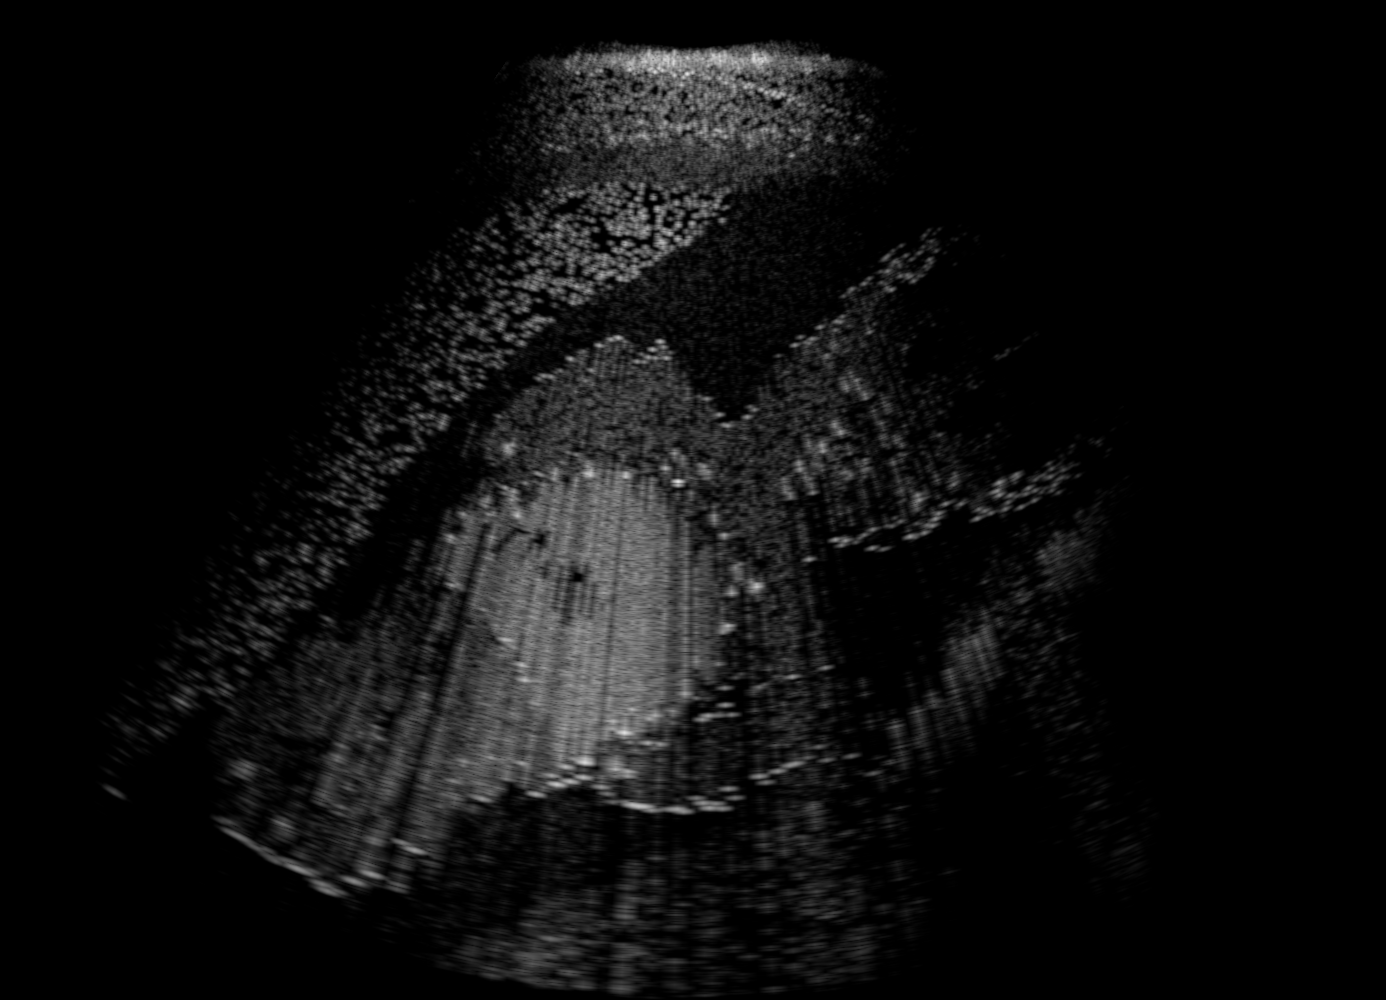

3.1 Full field-of-view Images

Above image translation has been demonstrated on patches. For the entire field-of-view (FoV) US images, patch fusion from image translation of non-overlapping patches would cause artifacts at image seams. Averaging overlapping patches, on the other hand, would blur the essential US texture. Although seamless tiling of US images is possible using graphical models [3], this requires prohibitively long computation time. Herein, we instead directly apply our trained generator on full FoV low-quality images, since the generator is fully convolutional and thus can operate on images of arbitrary size. Fig. 4 shows two examples of translated images by L2HMS and L2HMSA, demonstrating direct inference on full FoV images. While anatomical structures are well preserved and the effect of attenuation integral map is apparent, speckle texture appearance is seen to degrade slightly especially in the top image regions, where the ultrasound texture looking particularly different due to focusing difference and near-field effects.